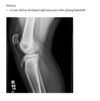

A 21-year-old man with worsening pain in the left wrist after an injury 6 months earlier (Fig. 2.13.1).

Figures 2.13.2 and 2.13.3 are of a 46-year-old man with wrist pain

Anteroposterior view of the left wrist

(Fig. 2.13.1) shows an ulna that is shorter than the

radius (i.e., negative ulnar variance or ulnar minus

variance) and a lunate that is sclerotic and some-

what irregular in shape.

Kienböck disease (i.e., lunatomalacia)

Kienböck disease, or lunatomalacia, is

osteonecrosis of the lunate. It is most common in

­ patients 20 to 40 years old and has a predilection

for the dominant hand in individuals involved

in manual labor.

Cause unknown

shortened ulna

in relation to the radius (i.e., negative ulnar variance

or ulnar minus variance) is seen in up to 75% of pa-

tients with lunatomalacia and is considered a major

cause of the disorder

The imaging findings, which do not always corre-

late with the patient’s symptoms, include increased

density or sclerosis of the lunate and, eventually, alteration in the normal bony shape with collapse

on radiographs.

For example, in a 46-year-old

man with wrist pain, a coronal T1-weighted image

(Fig. 2.13.2) demonstrates low signal intensity in

the lunate (arrow) and negative ulnar variance. The

gradient-recalled echo MR image (Fig. 2.13.3) shows

the signal intensity within the lunate to remain low

(arrow). These features are diagnostic of osteone-

crosis (i.e., Kienböck disease). Surgical intervention

includes lunate replacement, radial shortening, and

ulnar lengthening.